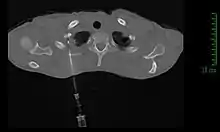

Modalités diagnotiques

Si la clinique et l'imagerie permettent à elles seules de poser le diagnostic de tumeur de Pancoast-Tobias, ce n'est que l'analyse d'une biopsie tissulaire qui permettra d'identifier le type de tumeur, et ainsi de guider le traitement[11].

La méthode de diagnostic la plus précise est la ponction percutanée trans-thoracique par ponction à l’aiguille, sous contrôle scanner, qui présente un rendement de 95 %[11],[21]. En cas d'échec, il est possible de réaliser une biopsie chirurgicale par thoracoscopie ou thoracotomie[11].

La fibroscopie bronchique est souvent peu contributive ; la localisation très périphérique de la tumeur la rend en effet inaccessible techniquement. La fibroscopie ne permet ainsi de réaliser des biopsies de la tumeur que dans environ 20 % des cas[21],[11].